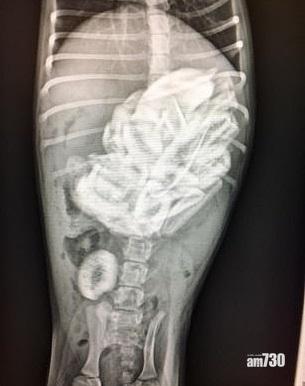

X光檢查發現狗狗胃部塞滿牛仔骨。(互聯網)

美國加州一隻6磅重的3個月大狗狗,早前被主人發現呆呆滯滯、沒精打彩,帶牠到獸醫診所接受X光檢查,赫然發現牠胃部竟塞滿46件牛仔骨,懷疑牠在主人不在場下狂食出事。薩克拉門托愛護動物協會的獸醫庫克施手術,幫狗狗取出胃部的一大堆牛仔骨,驚訝︰「一隻小小的6磅重狗狗,怎樣啃得下46件牛仔骨?」庫克說,暫未清楚是人類故意餵食,還是狗狗自己「摷」垃圾堆,誤食骨頭所致。